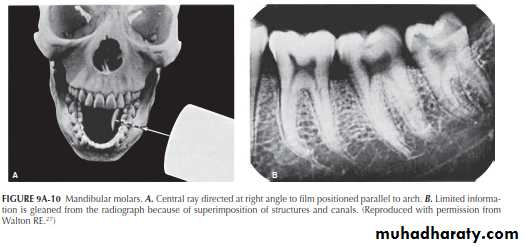

Mandibular Molars

Through the Walton projection (SLOB) , however, the roots will “open up.

”This is done by directing the central beam 20° to 30° from either the distal or the mesial (Figure 9A-11A).By applying Ingle’s rule (MBD: project the central beam from the mesial ), the buccal canals are toward the distal , the lingual canals toward the mesial .